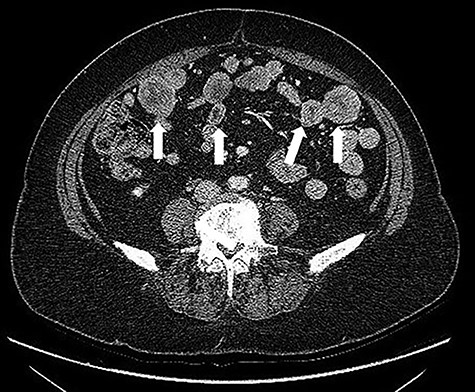

After multidisciplinary team discussion, patient was submitted to diagnostic laparoscopy. Intra-operatively, a friable and easily bleeding bulky pelvic mass was found (~5 × 8 cm), originating from the free margin of an ileal loop without infiltration of uterus and ovaries. Multiple secondary omental and mesenteric lesions were confirmed. A midline laparotomy was therefore performed, showing multiple omental and mesenteric secondary implants (Fig. 3) and a bulky pelvic mass originating from the small bowel (Fig. 4). Omentectomy, small bowel resection and complete removal of all mesenteric implants were performed. Postoperative course was uneventful with discharge on postoperative Day 6.